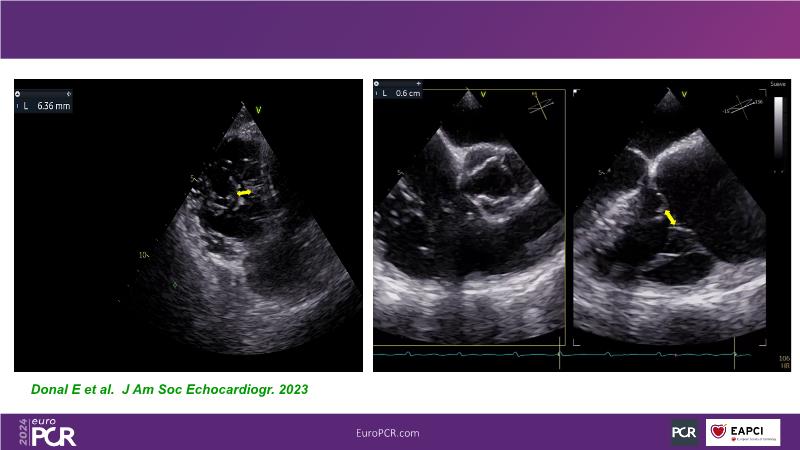

Transformative imaging in the clinical pathway of transcatheter tricuspid valve interventions

Explore this EuroPCR 2024 session for a comprehensive understanding of the imaging pathway in transcatheter tricuspid valve interventions, including diagnosis, therapy, and post-procedural follow-up, discover innovative, transformative imaging techniques such as 4D intracardiac echocardiography and dual-source photon-counting CT, and learn how these innovations can be applied in clinical practice.

- To gain a complete overview of the imaging pathway for transcatheter tricuspid valve interventions (from diagnosis to therapy to post-procedural follow-up)

- To learn innovative, transformative imaging techniques in transcatheter tricuspid interventions (e.g. 4D intracardiac echocardiography, dual source photon-counting CT)